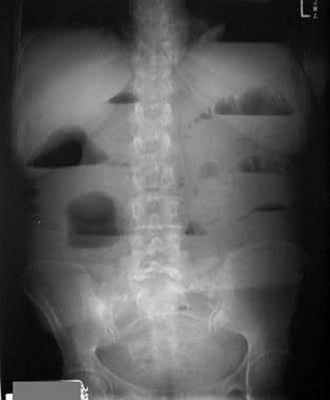

Рентгенологическое исследование является основным специальным методом диагностики ОКН. При этом выявляются следующие признаки:

- Чаша Клойбера – горизонтальный уровень жидкости с куполообразным просветлением над ним, что имеет вид перевернутой вверх дном чаши. При странгуляционной непроходимости могут проявляться уже через 1 час, а при обтурационной непроходимости — через 3-5 часов с момента заболевания. Количество чаш бывает различным, иногда они могут наслаиваться одна на другую в виде ступенчатой лестницы.

- Кишечные аркады. Получаются, когда тонкая кишка оказывается раздутой газами, при этом в нижних коленах аркад видны горизонтальные уровни жидкости.

- Симптом перистости (поперечная исчерченность в форме растянутой пружины) встречается при высокой кишечной непроходимости и связан с растяжением тощей кишки, имеющей высокие циркулярные складки слизистой. Контрастное исследование желудочно-кишечного тракта применяется при затруднениях в диагностике кишечной непроходимости. Больному дают выпить 50 мл бариевой взвеси и проводят динамическое исследование пассажа бария. Задержка его до 4-6 часов и более дает основание заподозрить нарушение двигательной функции кишечника.

Рентгенологическая диагностика острой кишечной непроходимости. Уже через 6 ч от начала заболевания имеются рентгенологические признаки кишечной непроходимости.